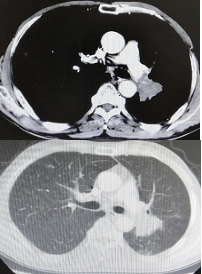

影像学-增强CT检查:左肺见不规则软组织影,包绕肺门结构,病变轴位长径约7.5cm,左肺散在结节影,最大约4.5cm;纵隔、肺门见多发淋巴结肿大,纵隔7组短径约2.0cm。

CT检查——基线

靶病灶:左肺病灶,75mm;左肺转移病灶,45mm;纵隔淋巴结,20mm;总和为140mm

非靶病灶:左肺多发转移;左肺门淋巴结转移。